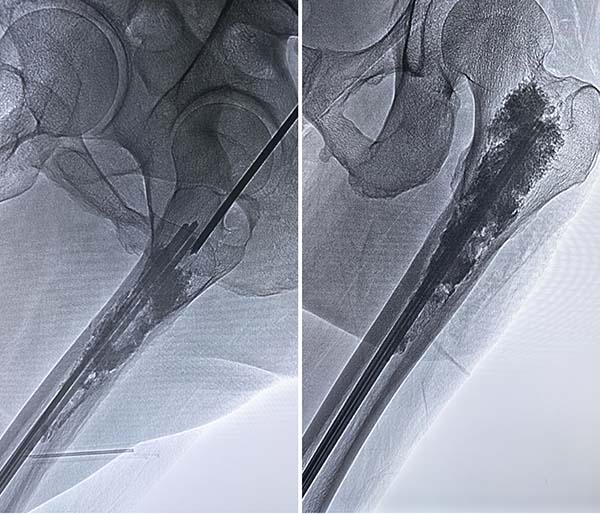

手术在DSA介入手术室顺利开展,由张开贤现场指导,于世平主任团队密切配合、协同发力。手术采用DSA实时影像精准定位病灶,分步有序开展诊疗操作:首先通过微波消融技术,利用高温精准灭活肿瘤细胞,有效控制肿瘤进展、缓解患者疼痛;随后在影像引导下精准实施经皮内克氏针固定术,为受损股骨提供稳固支撑,有效降低病理性骨折风险;最后行骨水泥成形术,将骨水泥精准注入病变骨骼区域,进一步加固骨骼强度、恢复骨骼稳定性。全程微创精准、出血少、创伤小,圆满达成手术目标,充分彰显了联合微创技术的临床优势。